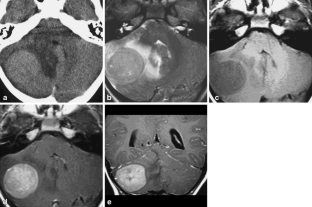

Magnetic resonance imaging spectrum of medulloblastoma

Two medulloblastoma variants were recently added to the WHO classification of CNS tumours. We retrospectively analysed the imaging findings of 37 classic and 27 cases of variant medulloblastomas to identify imaging characteristics that might suggest a particular MB subtype.

Sixty-four patients from three institutions were included. Location, tumour margins, signal intensities on conventional MRI, enhancement pattern, the presence of haemorrhage, calcifications and hydrocephalus were recorded and analysed. Signal characteristics on diffusion-weighted MR images and MR spectra were evaluated when available.

Thirty-seven classic type of MB (CMB), twelve cases of desmoplastic/nodular medulloblastoma (DMB), nine medulloblastomas with extensive nodularity (MB-EN), five cases of anaplastic and one of large-cell medulloblastoma were included. Fifty of 64 tumours were located in the 4th ventricle region. On T2WI, CMB were all hyperintense, whereas DMB and MB-EN showed isointensity in up to 66%. One third of the classic MB showed only subtle marginal or linear enhancement. All medulloblastoma variants showed marked enhancement.

The results of our study suggest: (a) an age-dependent distribution of MB variants, with DMB and MB-EN more common in younger children; (b) a female predominance in DMB; (c) a more common off-midline location in DMB (50%) and MB-EN (33%) variants.

Fig. 1